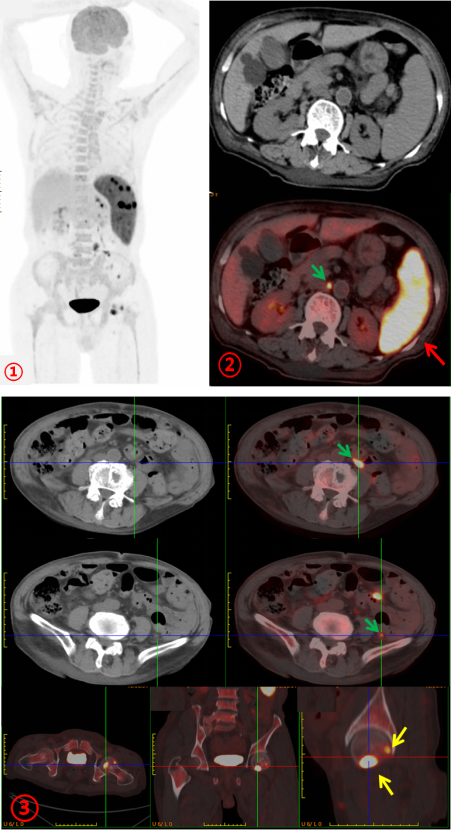

為進一步明確病情,完善PET/CT檢查。PET/CT示:脾臟彌漫性增大伴FDG代謝明顯不均勻增高(SUVmax約22.3;圖1、2,紅箭),腹膜后及腹腔內(nèi)多發(fā)FDG代謝增高結節(jié)(SUVmax約8.8;圖1、2、3,綠箭),全身多發(fā)骨骼FDG代謝增高,左股骨頭為著,(SUVmax約11.7;圖1、3,黃箭),骨骼未見明顯破壞。PET/CT診斷為淋巴瘤?;颊唠S后完善骨髓活檢,病理診斷為:小B細胞淋巴瘤。